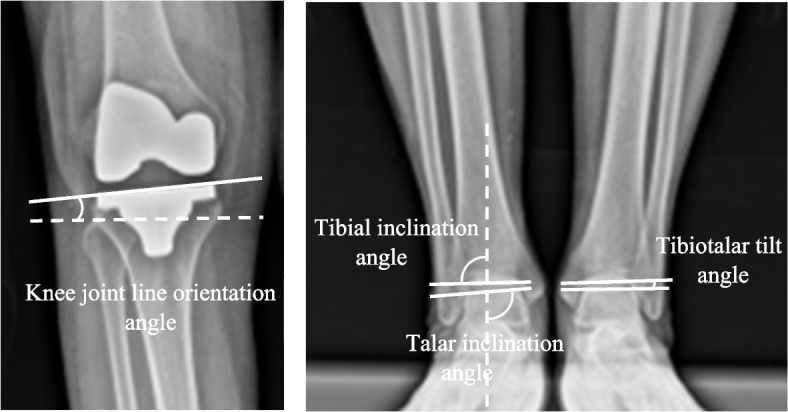

Results: Postoperative hip-knee-ankle angles between the FA and MA groups were similar (2.4° versus 2.4°, P = 0.952). Knee joint line orientation was significantly more parallel to the floor in the FA group (3.0° versus 4.7°, P < 0.001). There was no significant difference in ankle joint line orientation relative to the floor in the FA and MA groups (91.0° versus 92.4°, P = 0.099 for tibial plafond inclination and 92.5° versus 93.2°, P = 0.564 for talar dome inclination). However, in knees with preoperative varus with apex distal joint line orientation (coronal plane alignment of the knee (CPAK) classification type I), FA significantly achieved a more parallel knee and ankle joint line orientation relative to the floor (3.1° versus 5.1°, P = 0.002 for knee and 91.0° versus 93.5°, P = 0.028 for tibial plafond inclination). FA can obtain a balanced knee with significantly lower posteromedial releases (23.3% versus 76.7%, P < 0.001), with no superficial MCL release needed (0% versus 6.67%, P < 0.01). The FA group achieved significantly higher FJS at 3 months (53.3 versus 46.0, P = 0.015) and 6 months (67.8 versus 57.8, P < 0.001) with a higher patient satisfaction score (79.2 versus 84.3, P = 0.001).

Conclusion: Functional alignment can control the overall lower limb alignment similarly to mechanical alignment, with a knee joint line more parallel to the floor. Additionally, the ankle joint line was more parallel in knees with CPAK type I. FA can also provide a more balanced knee with less soft tissue release, a higher functional score, and greater patient satisfaction compared to mechanical alignment.